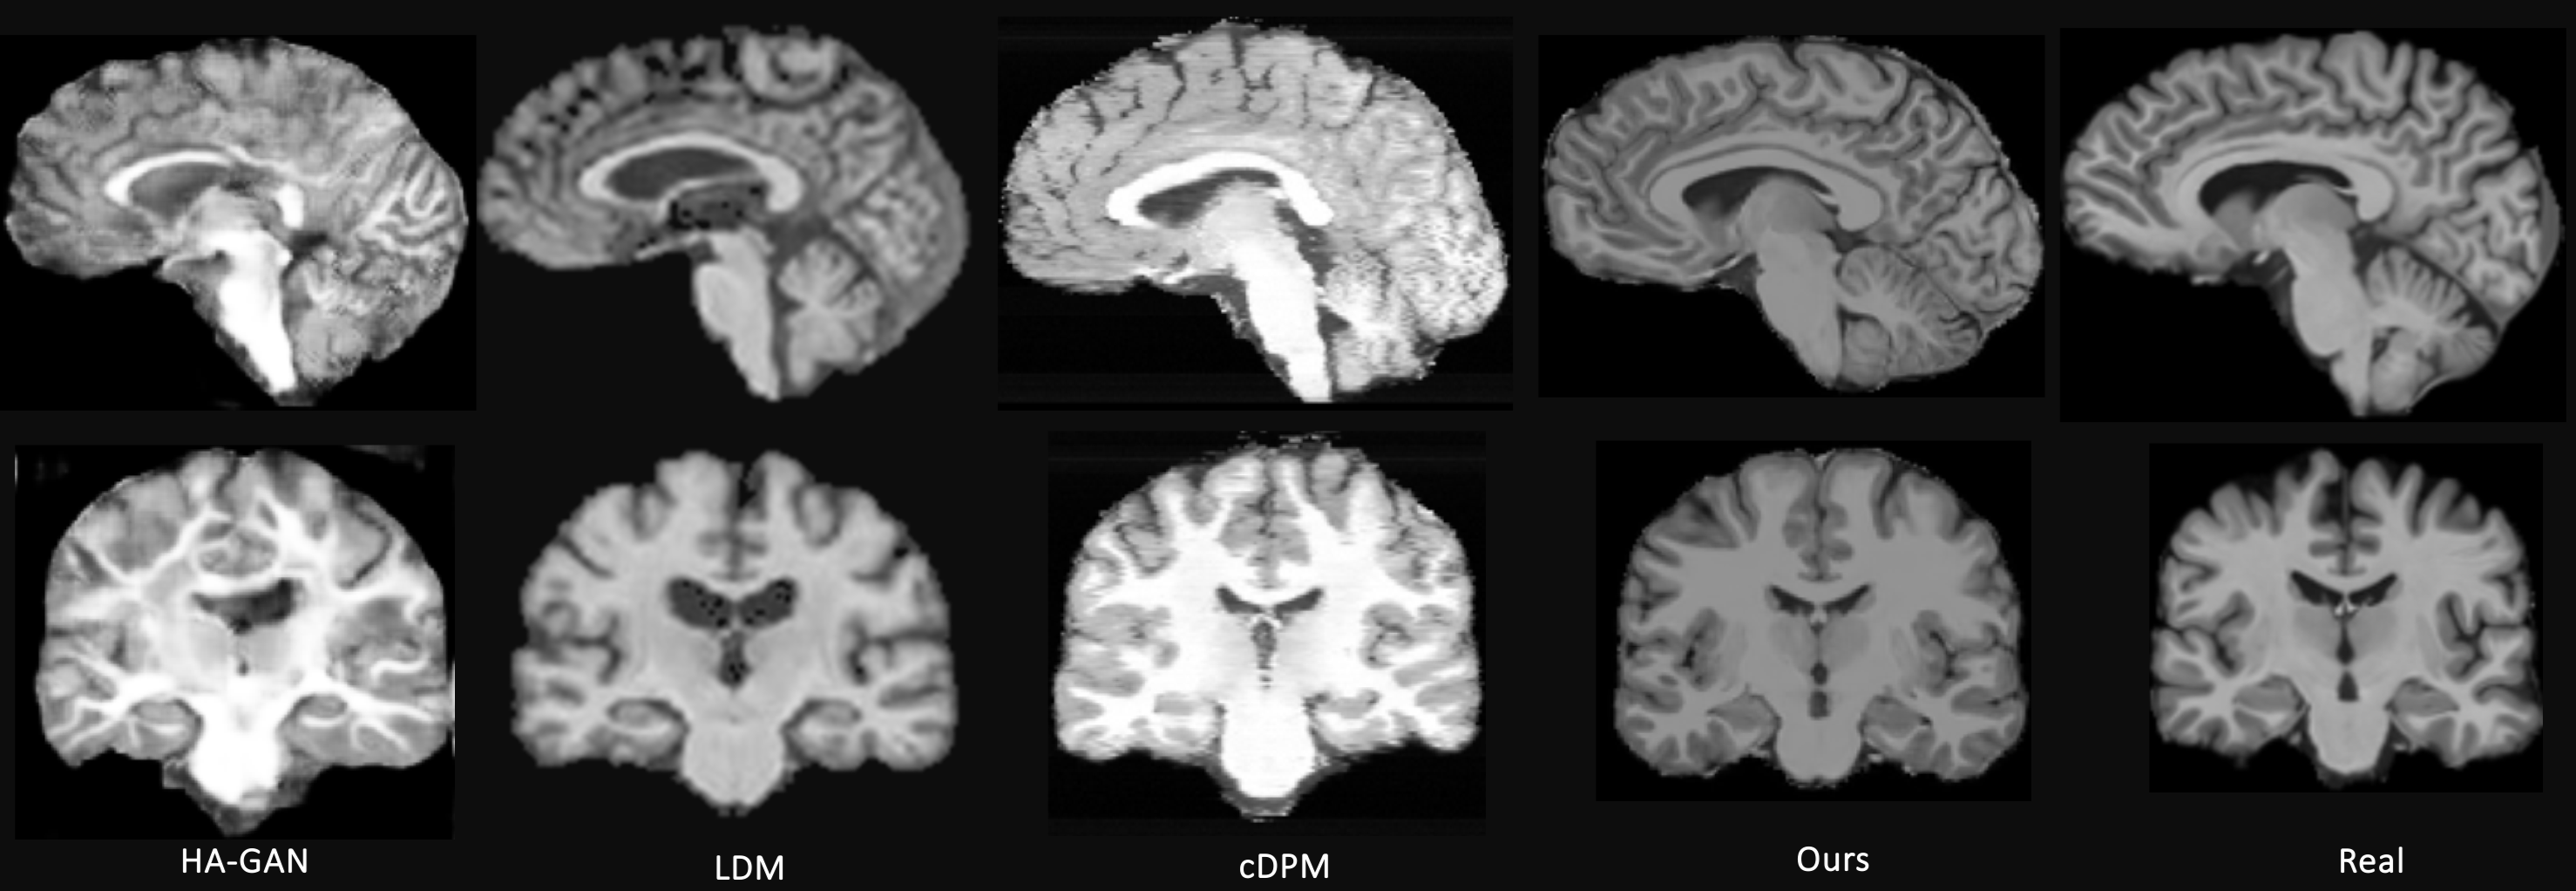

Figure 3: Show cases. 2 views of real MRI vs synthetic MRIs generated by 4 models. Our model can produce visually similar MRI to others but we can do counterfactual generation.

By preforming random intervention, 400 counterfactuals are synthesized. We then compare with synthetic MRIs from recent generative models and also evaluate it anatomical plausibility to qualify its value for neuroimaging studies. The comparison methods include GAN models like CCE-GAN [30], VAE-GAN [12], α𝛼\alpha-WGAN [10], and HA-GAN [26]; and diffusion models like latent diffusion model (LDM) [21] and cDPM [18]. Qualitative results of all 7 models are shown in Appendix while only the best four are shown in Fig. 3 due to space limitations. Of those four methods, HA-GAN was the only method that was not able to produced the MRIs that looked like those of healthy controls. On the other side LDM produces the noisiest MRI and the MRI of cDPM has clear slice artefacts. In contrast, the MRI of our model shows clear gray-matter boundaries and looks most similar to the real MRI. Finally, our model is much faster than the diffusion-based method as their is no need for the multi-step diffusion process.